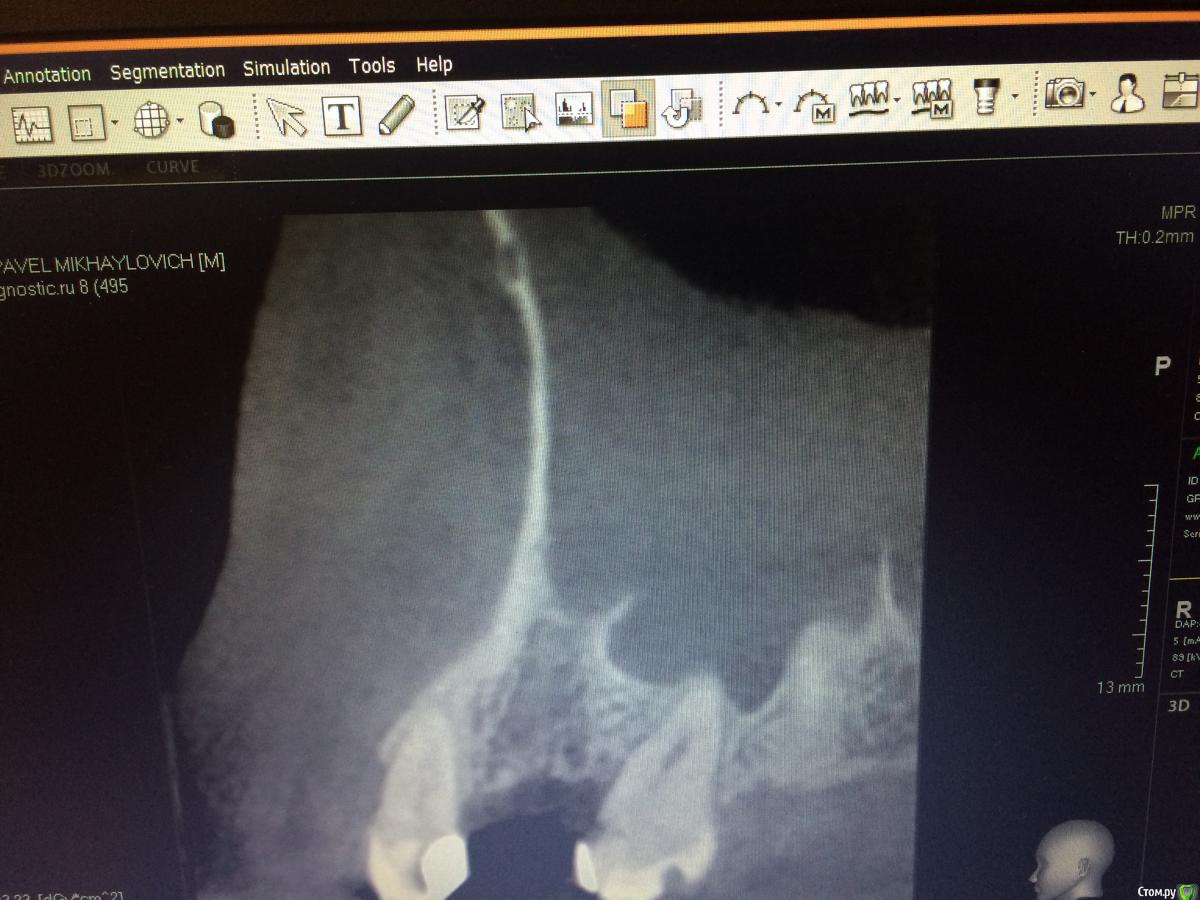

Graffwoman Опубликовано 25 февраля, 2018 Автор Поделиться Опубликовано 25 февраля, 2018 (изменено) внесу свою лепту Сосудосуживающий капли в нос на 10 дней - в каждый носовой ход Амоксиклав 1000 мг по 1 2 рд 5 дней либо супракс либо таваник - их легче принимать Бифиформ АциполНимесил 100 мг по 1 пакет 2 рд 7 дней Хлоргексидин или мирамистин - ротовые ванночки до 6 раз в день, потом сразу солкосерил дентальный наносить - он держится намного лучше других гелей и паст ,хватает трех раз в день Ну ,вообщем, это стандартный набор Из протокола хотел выяснить 1. чем сверлились ? был ли использован набор для закрытого синуса ?2. когда удаляли ( если это были Вы ) качественно ли был выполнен корежат?3.торк ?не вижу смысла трогать имплантат сейчас .Пусть заживает вторичным натяжением .Приживется - хорошо ,нет - переставите .Спасибо1.Стандартный набор Osstem2.Хороший вопрос.Прошло 1,5 года с момента удаления.Причину удаления сходу не вспомню ,но процесс был хроническим,без признаков воспаления.На верхушке корня после удаления была прикрепленная гранулема. .Кюретаж был ,как считали тогда- легкий (гранулема то вышла ),но качественный.Проба на соустье после удаления отрицательная.Сгусток формировался слабо,в лунку рыхло положила губку с йодоформом. Неожиданно лунка заживала плохо,вялотекущий альвеолит. Дополнительный неагрессивный кюретаж и промывание ХГ. .Но.... Через год- КТ и поняли,что кость не полноценная. На слизистой десны вроде легкое углубление-точка. Не придали значения,может,ревизию надо было сделать??? .Больше насторожил обьем слизистой в пазухе-до 25 мм,на сегодня -до 10). Долго ходил по ЛОРам -толку никакого. Решили оставить в надежде,может кость сформируется.,теперь снова вернулись.Всю остальную историю уже знаете. Прилагаю снимок первого КТ, по поводу размытой границы гайморовой -ничего пока не могу сказать,кажется,это просто такой ракурс. .3.Торк 45Сейчас принимает ципрофлоксацин третьи сутки по 500 мг 2р/д,антигистаминные, нимесил получается 2р/д,(тк к вечеру стал ныть снова),противогрибковые и для флоры кишечника. Как думаете ,а боль в проекции верхушки имлантата -откуда ? Изменено 25 февраля, 2018 пользователем Graffwoman Ссылка на комментарий

rytovst Опубликовано 26 февраля, 2018 Поделиться Опубликовано 26 февраля, 2018 боли одного характера ,одинаковой силы ?возможно была перфорация при удалении - трудно судить / много времени прошло вначале темы на прицельном снимке с медиальной стороны 2 витка резьбы в пазухе- может быть искажение.тут разговаривал с другим имплантологом - ставит смело при перфорациях Шнайдеровой - я не рискую.Откуда боль ? Вопрос хороший . как с перкуссией соседних зубов ? Ссылка на комментарий

TIGER Опубликовано 27 февраля, 2018 Поделиться Опубликовано 27 февраля, 2018 там синусит,сделайте КТ пазухи и всё проясниться!По импаланту:ставьте формик и всё Ссылка на комментарий